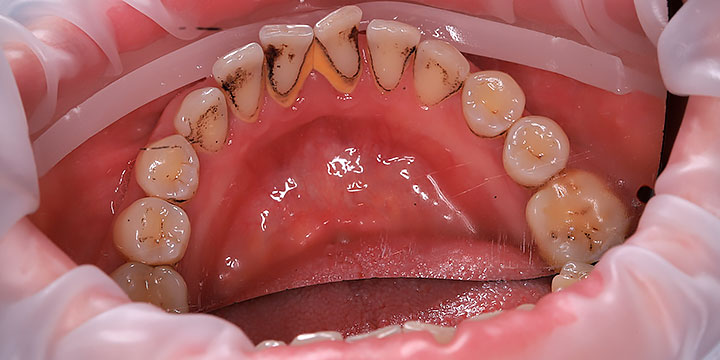

В Дева-Дент я работаю стоматологом-гигиенистом с уклоном в хирургию и пародонтологию. При гигиене я особенно обращаю внимание на состояние дёсен и работаю по протоколу пародонтологической настороженности.

Качественная гигиена — это мой конёк!

Прекрасно понимаю, что визит к стоматологу может вызывать тревогу. Поэтому я делаю все возможное, чтобы создать максимально комфортную и спокойную атмосферу, подробно объясняю каждый этап процедуры и всегда открыт для ваших вопросов. Моя миссия проста: сохранить ваши зубы здоровыми и красивыми на долгие годы с помощью эффективной профилактики.